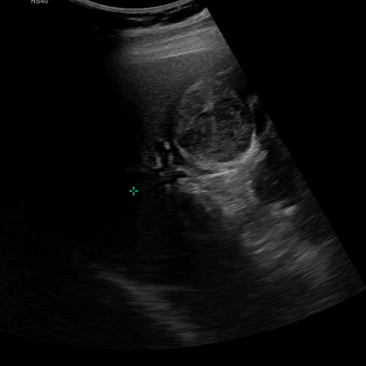

https://blog.naver.com/ejercicio/223164810850 상기 환자 24년도 진료 2회 .. 그리고 25년도 방문 어제부터 식후 명치/우상복부/등쪽 누르는 통증... 저녁에 자다가 불편해서 깰정도.. ~2시간? 누르는 느낌.. ; 증상은 아주 명료하지 않은데.. (담낭산통, 담석증으로 보기엔) 본인은 담낭걱정... 촉진시 압통은 없으며... 역시나 의사이므로 증상을 상의하고, 배제하기 위한 초음파를 결정함 담낭 및 담관에 특이소견 없음. 지금은 증상이 거의.. 증상적 투약 후 변화있는지 관찰/추적하기로 함 그 외 비장과, 왼쪽 신장사이에 작은 결절이 보이는데 부비장일수도 있겠다. 1년뒤 추적하기로 함 부비장과 부신우연종의 구별이 쉬울 것인가? https://blog.naver.com/ejercicio/221548748297 우측일때는 부비장은 아니니... 부신우연종 https://blog.naver.com/e